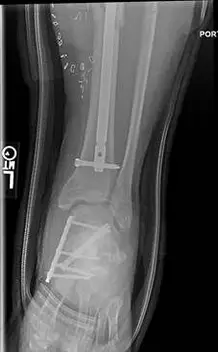

These are pics of the plate and screws stabilizing the fractures after ex-fix was removed. An IM rod was also placed for a tibia fracture.